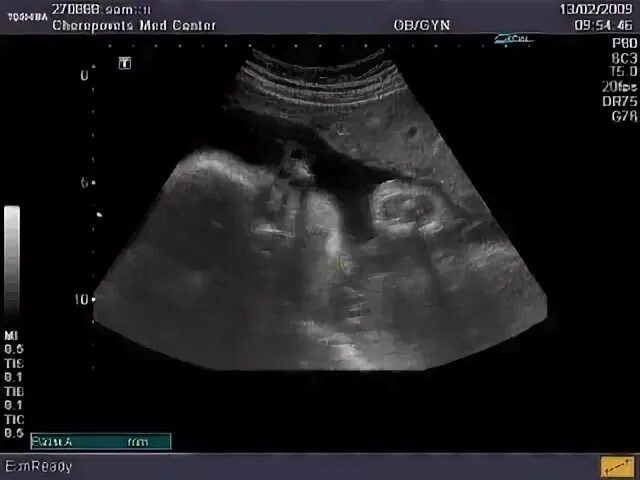

Узи в лабинске